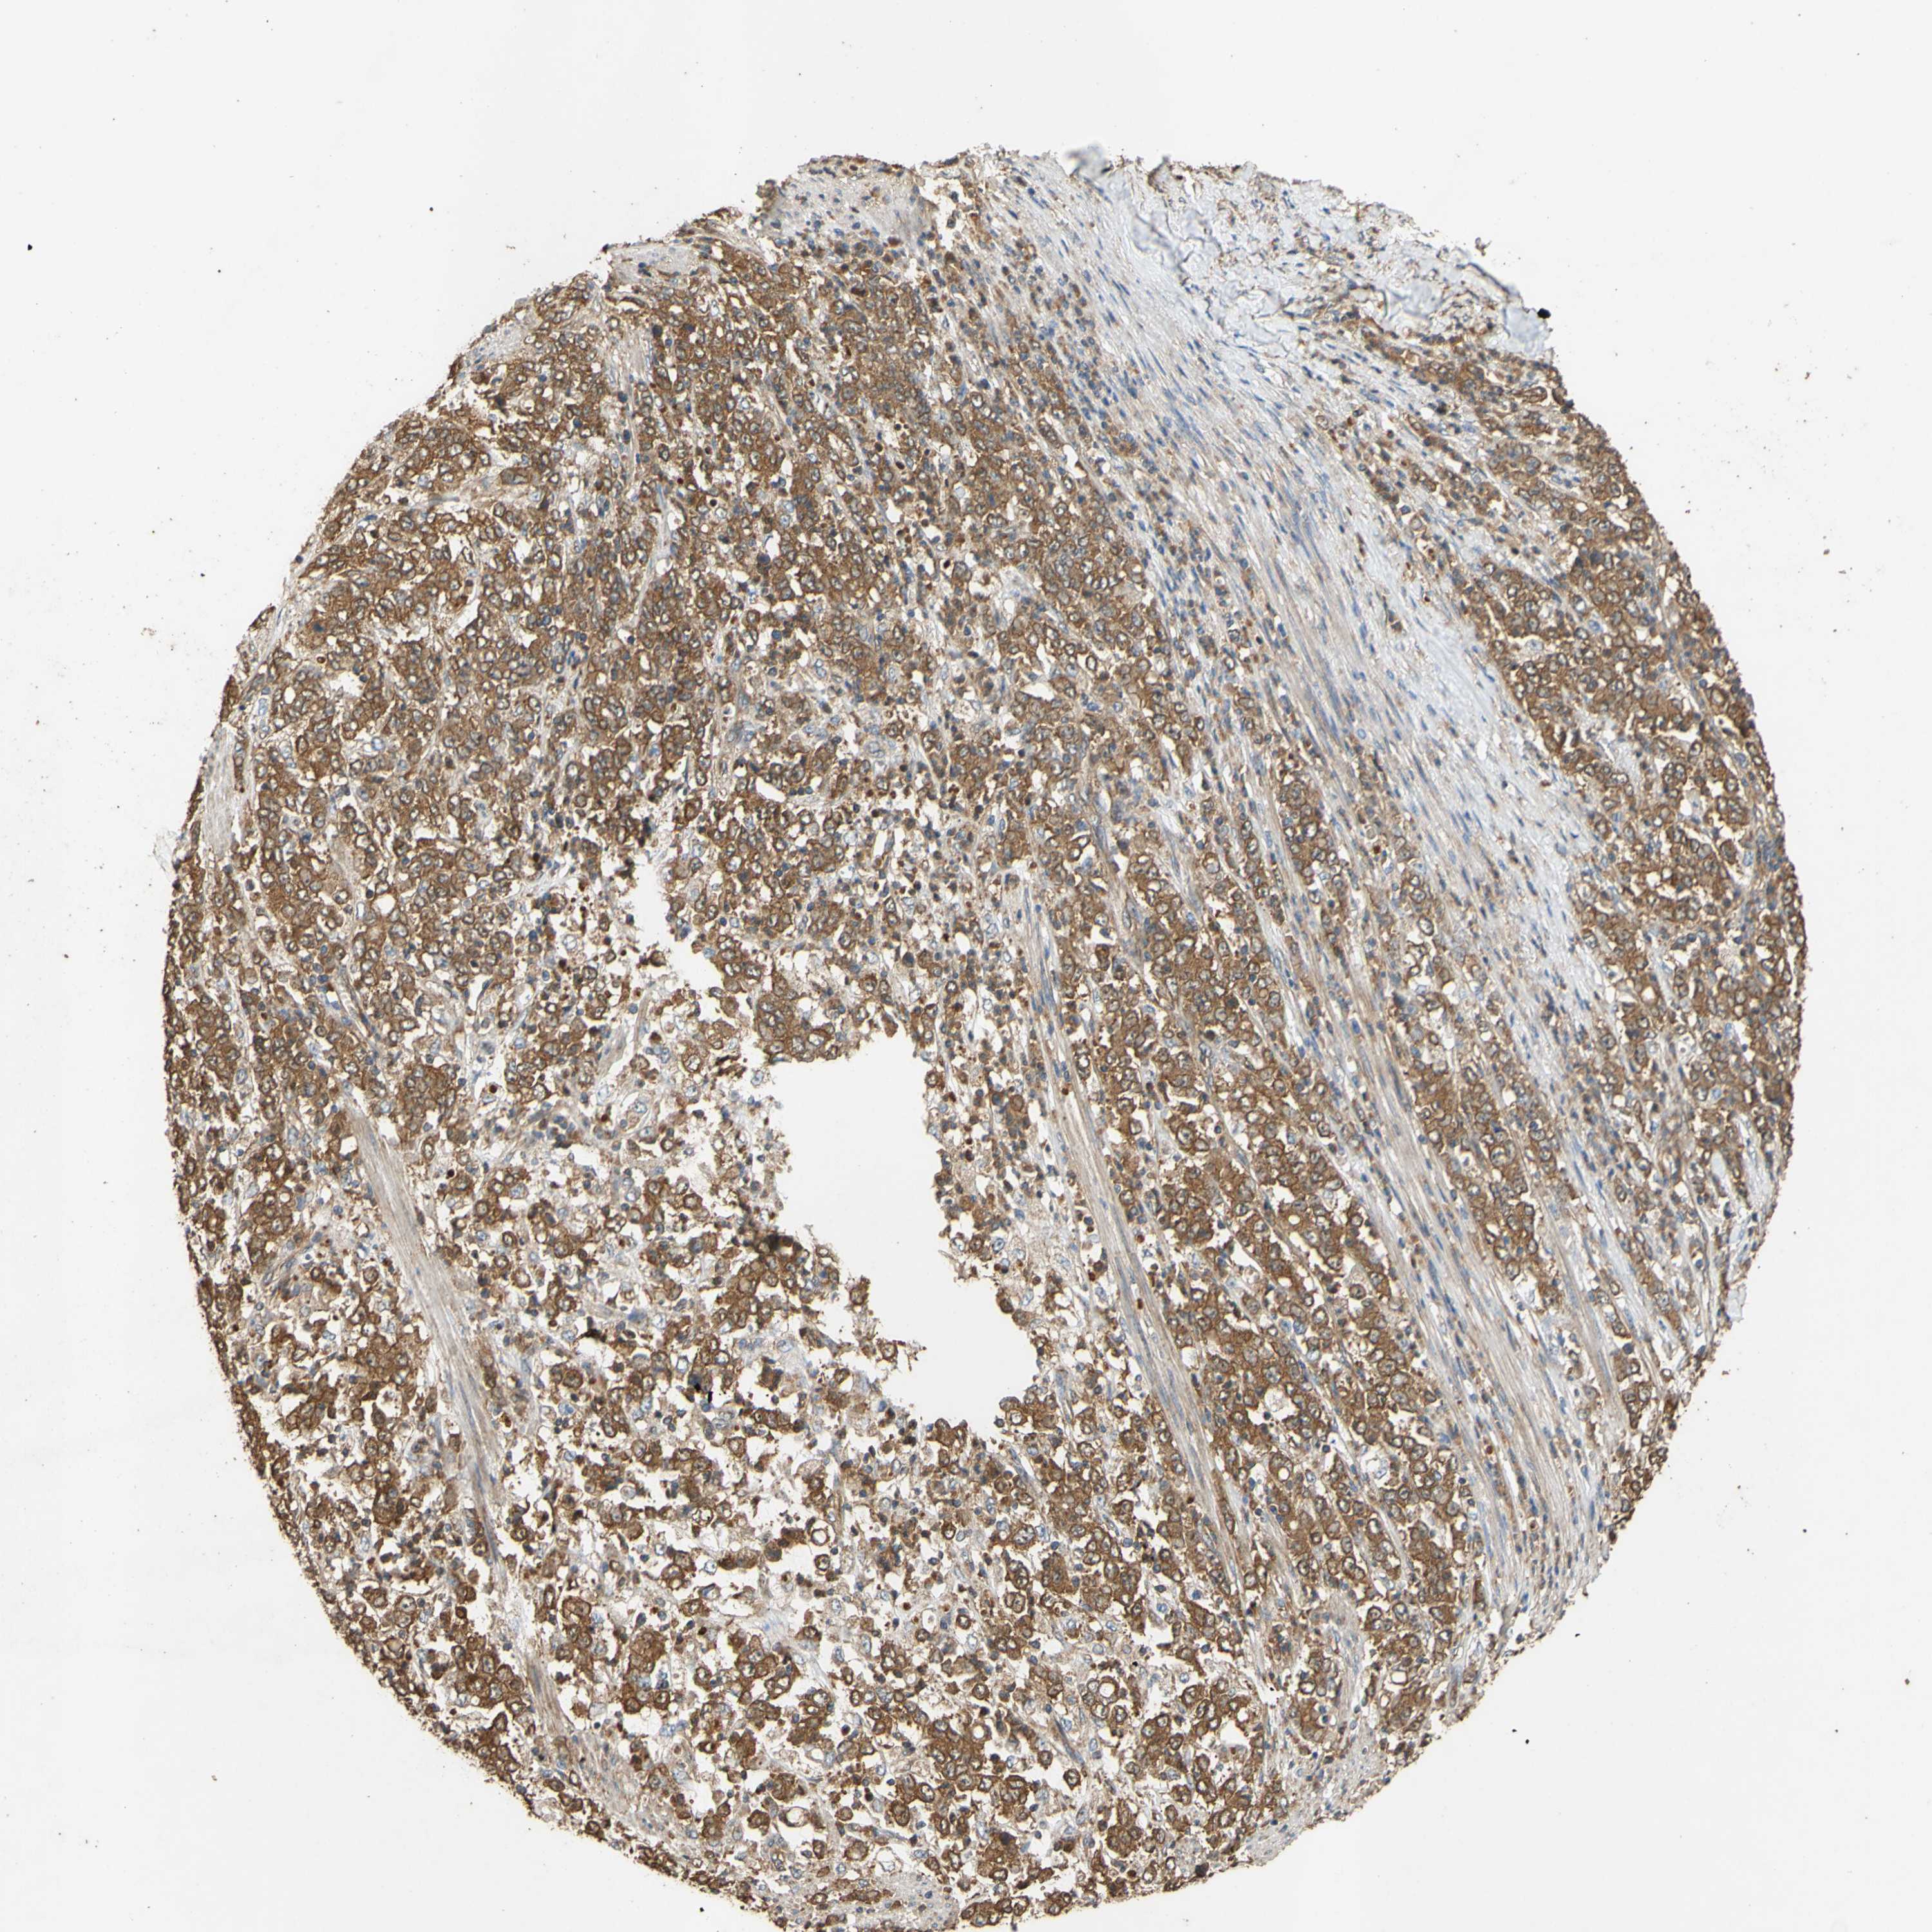

STOMACH CANCER - Protein expressioni

A mouse-over function shows sample information and annotation data. Click on an image to view it in a full screen mode. Samples can be filtered based on level of antibody staining by selecting one or several of the following categories: high, medium, low and not detected. The assay and annotation is described here.

Note that samples used for immunohistochemistry by the Human Protein Atlas do not correspond to samples in the TCGA dataset.

Antibody stainingi

Antibody staining in the annotated cell types in the current human tissue is reported as not detected, low, medium, or high, based on conventional immunohistochemistry profiling in selected tissues. This score is based on the combination of the staining intensity and fraction of stained cells.

Each image is clickable and will lead to virtual microscopy that enables deeper exploration of all samples and also displays staining intensity scores, fraction scores and subcellular localization as well as patient and tissue information for each sample.

Antibody HPA057242

Antibody CAB011235

Staining

High

Medium

Low

Not detected

Intensity

Strong

Moderate

Weak

Negative

Quantity

>75%

75%-25%

<25%

None

Location

Nuclear

Cytoplasmic/membranous

Cytoplasmic/membranous,nuclear

Adenocarcinoma, NOS

Adenocarcinoma, High grade